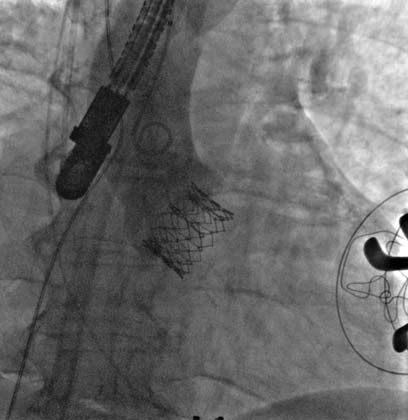

Figure 6. TAVR valve positioning at the level of the aortic annulus under angiographic control.

Rapid pacing was initiated at 150 bpm and the Sapien XT valve was slowly manually expanded in the native aortic annulus with 31ml of contrast in the inflation device (Figure 7A). After valve implantation the angiogram and TEE showed a stable position of the valve with significant para-valvular leak due to underexpansion. Rapid pacing was reinitiated and balloon post-dilation was performed with 33 ml of contrast for the optimization of valve deployment (Figure 7B). An optimal position and hemodynamics of the Sapien XT valve was achieved with mild residual para-valvular leak (Figure 8). Surgical closure of the apex and of the chest incision was completed.

Figure 7. Progressive valve expansion (Figure 7A) and post-dilatation with a higher balloon contrast volume to optimize implantation (Figure 7B).